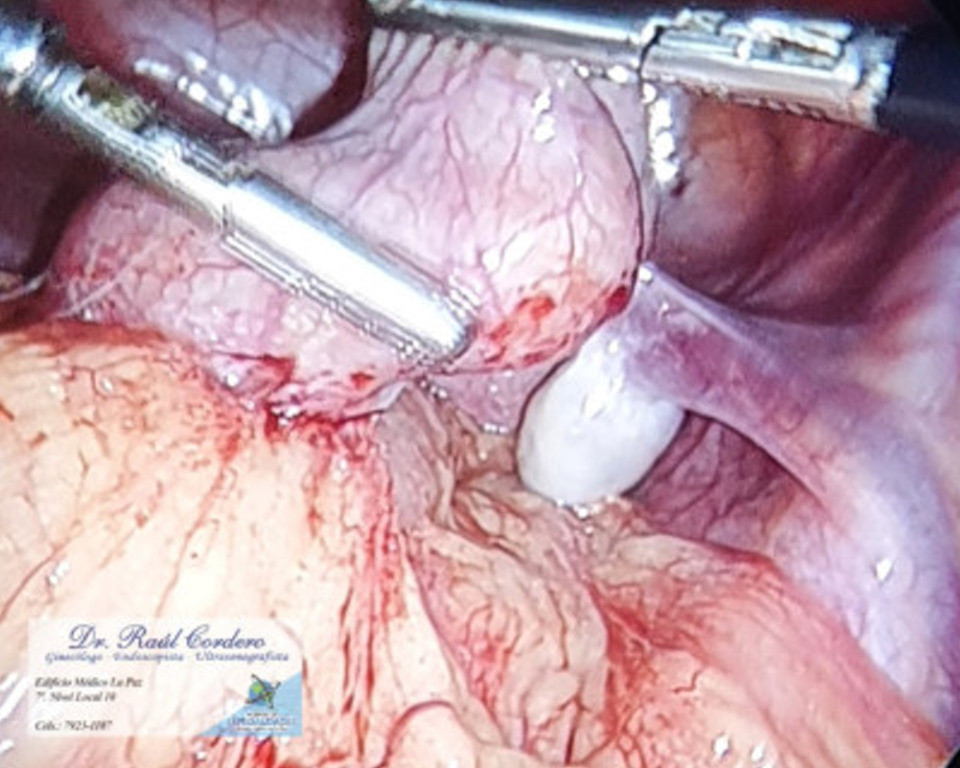

Miomectomia por vídeo laparoscopia